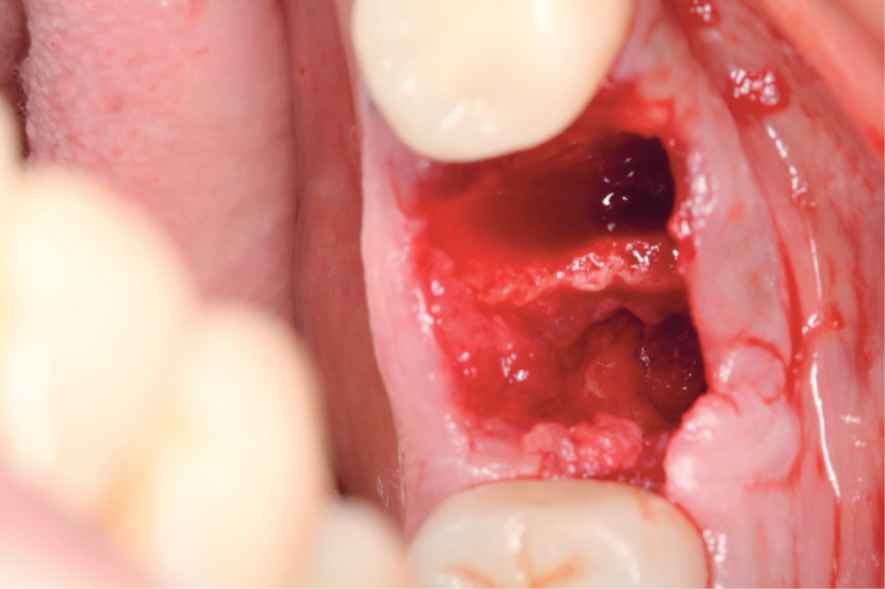

Na antissepsia intraoral da paciente, foi utilizada umasolução de digluconato de clorexidina a 0,12% para bochechoda cavidade oral. A equipe foi paramentada, a mesa cirúrgicafoi montada e, com uma pinça Allis, gaze estéril e solução de digluconato de clorexidina a 2%, foi realizada a antissepsia extraoral em movimentos de raios de sol, sendo a paciente paramentada. Na etapa da anestesia, realizou-se o bloqueio do nervo alveolar inferior, nervo lingual e nervo bucal do lado direito usando a técnica anestésica correspondente, com três tubetes de anestésico para o procedimento cirúrgico (mepivacaína 2% com vasoconstritor epinefrina 1:100.000). Nestas etapas também foram administradas anestesias infiltrativas na mucosa da região operada como forma de hemostasia. A cirurgia de exodontia foi executada com a técnica atraumática sem abertura de retalho, para evitar o máximo de trauma, visando à preservação das estruturas ósseas circunjacentes. Após a anestesia, com uma lâmina de bisturi 15C, foi realizada a incisão intrassulcular. Em seguida, utilizou-se o periótomo curvo para auxiliar o processo de luxação, rompendo as fibras do ligamento periodontal, com a alavanca apical reta número 301 fazendo a luxação do dente, extraindo-o com um fórceps 17. Finalizada a extração com a cureta de Lucas, foi realizado o debridamento do alvéolo por meio da curetagem da lesão e verificado que as paredes alveolares se apresentavam intactas para a instalação do implante. O material não foi enviado para biopsia (Figura 3).